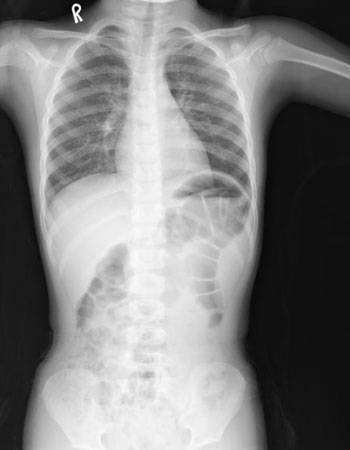

在《酉陽雜俎》裡,曾經記錄了這樣一片鏡子:「秦鏡舞溪古案石窟,有方鏡徑丈餘,照

人五臟,秦皇世號為“照骨寶”,在無勞縣境山。」

這是在秦朝時代,有一個石洞裡藏了一片長一丈多的方鏡,大小有三公尺長,這片鏡子可

以照出人的五臟,所以秦始皇把它叫做「照骨寶」,這個石洞位於無勞縣境的山中。

秦始皇時代大概對於這種超越時代的 X 光機類的儀器特別有興趣吧,因為他擁有的超時

代寶物並不只是照骨寶這一件,還有別的。

在《西京雜記》中記載著,秦始皇在首都咸陽的宮府庫中藏有許多的寶物,其中有一件奇

特的寶物,它的功能是這樣的:「有方鏡,廣四尺,高五尺九寸,表裡有明。直來照之,

影則倒見。以手掩心而照之,則知病之所在,見腸胃五臟,歷然無礙。又女子邪心,則膽

張心動。始皇常以照宮人,膽張心動者則殺之。」

這是一面秦始皇宮中藏有的寶鏡,高大概是一個人的高度,寬度大概一公尺多,在外面和

裡面都有光源,只要用手掩著心在鏡前照著,就可以知道疾病的位置,這面鏡子的解析度

很好,照上去腸胃五臟都可以看得清清楚楚。而它超越現代科技之處,是這面鏡子除了能

照出內臟的清楚影像外,連人的情緒都可以照得出來。如果一個人有了邪心,也就是想要

幹些什麼壞事,就會照得出膽和心臟異常的動靜,可以看得出這人想要做些什麼犯禁的事

。所以秦始皇常拿這東西來照宮裡面的宮女,只要有誰想要圖謀不軌,就會立刻把她殺掉

。

這個儀器除了和我們熟知的 X 光機、核磁共振儀功能接近外,還能夠照出人的情緒和圖

謀,可以說是一件超時代的奇異科技產品了。